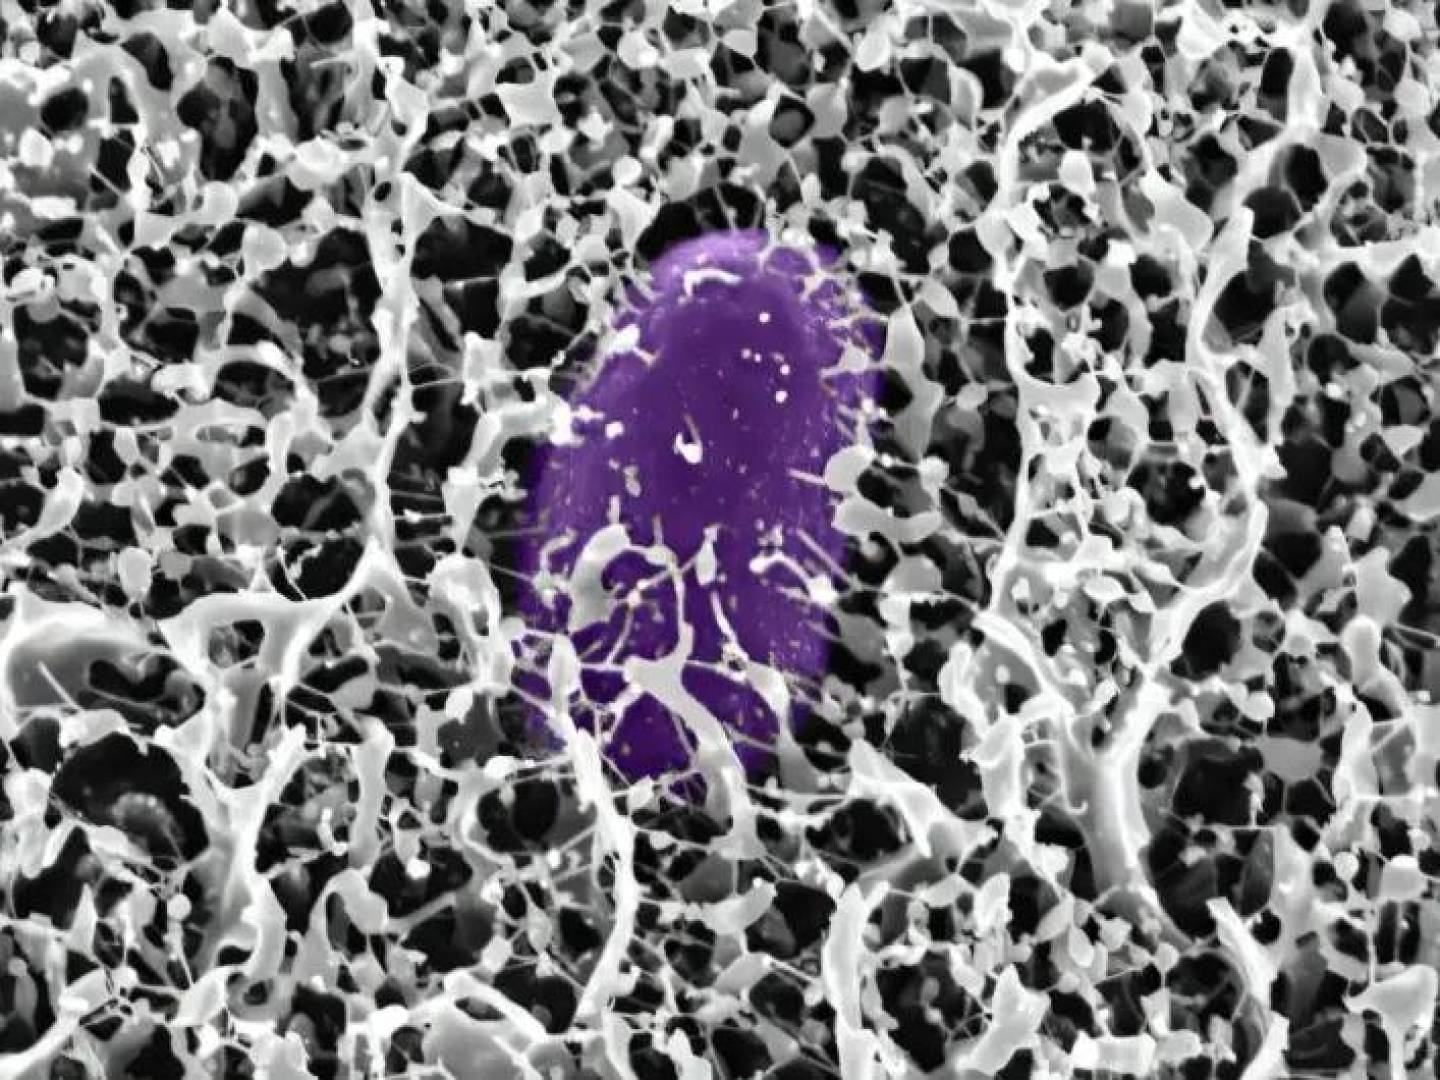

يقوم الخبراء باختبار لقاح يأمر  الجسم بتعقب خلايا السرطان وقتلها، ومنع عودتها. يُعرف هذا اللقاح باسم BNT116، وتنتجه شركة BioNTech، ويستهدف سرطان الرئة ذا الخلايا غير الصغيرة، وهو أكثر أنواع المرض شيوعاً.

ويستخدم اللقاح تقنية (mRNa)، المماثلة لتلك المستخدمة في لقاحات كوفيد-19، ويعمل على تقديم علامات الورم الخاصة بسرطان الرئة ذي الخلايا غير الصغيرة إلى الجهاز المناعي، لتحفيزه على محاربة الخلايا التي تحمل هذه العلامات.

والهدف هو تعزيز الاستجابة المناعية ضد السرطان من دون الإضرار بالخلايا السليمة، على عكس العلاج الكيماوي.